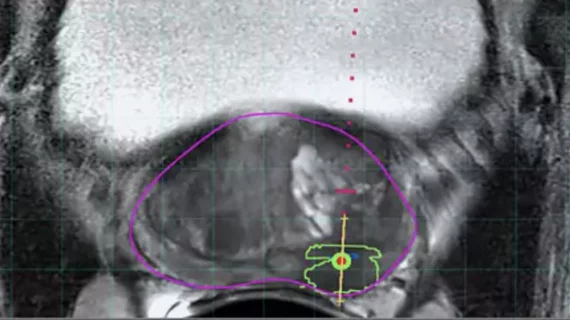

A significant advancement in the last decade has been the incorporation of pre-biopsy MRI information to target biopsies to suspicious lesions, rather than relying on random sampling. MRI-ultrasound fusion biopsy combines the strengths of both imaging modalities: the superior lesion detection of MRI with the convenience and real-time guidance of ultrasound.

The workflow typically involves the patient getting a multiparametric MRI of the prostate before biopsy. If the MRI shows one or more suspicious lesions (assigned PI-RADS scores), these can be targeted. There are two main approaches:

- Cognitive fusion biopsy: The operator (urologist or radiologist) performs a TRUS biopsy while mentally projecting where the MRI lesion is located in the prostate. For example, if MRI shows a lesion in the anterior horn of the peripheral zone at mid-gland on the right, the operator will aim the ultrasound-guided needle to that approximate location. This method requires skill and spatial understanding, but no special software. It has a learning curve and somewhat variable accuracy.

- Software-based MRI-US fusion biopsy: Here, dedicated fusion platforms/software are used. The MRI images (with contoured lesions) are loaded into an ultrasound machine or an attached computer. During the TRUS exam, the system electronically or mechanically fuses the MRI and real-time ultrasound by coregistration (often by aligning prostate contours or using fiducial markers). This allows the MRI targets to be superimposed on the ultrasound screen. The operator can then direct the biopsy needle precisely into the MRI-defined lesion. Fusion devices often use electromagnetic tracking or stepper motors to know the ultrasound probe position in space, enabling accurate alignment. This approach is more technologically complex but can yield very precise targeting within a few millimeters of the intended target.

From the perspective of ultrasound’s role, it remains central. Even in MRI-fusion biopsy, the actual needle placement is done under ultrasound guidance. MRI by itself can be used in-bore for direct MRI-guided biopsy, but that is resource-intensive (requiring an interventional MRI suite) and time-consuming (each needle placement under MRI is lengthy). In practice, MRI-guided in-bore biopsies are rare; MRI–US fusion performed by ultrasound machines in clinic is far more common due to its efficiency. Fusion devices resolve the prior issue that MRI is not real-time – by linking MRI to ultrasound, the operator can see and fire at the target during an office procedure, which is a major workflow advantage. As Chen et al. summarized, “MRI–ultrasound fusion combines the high sensitivity of MRI with the practicality of ultrasound guidance”. It effectively boosts the yield of ultrasound-guided biopsy to what MRI can reveal.